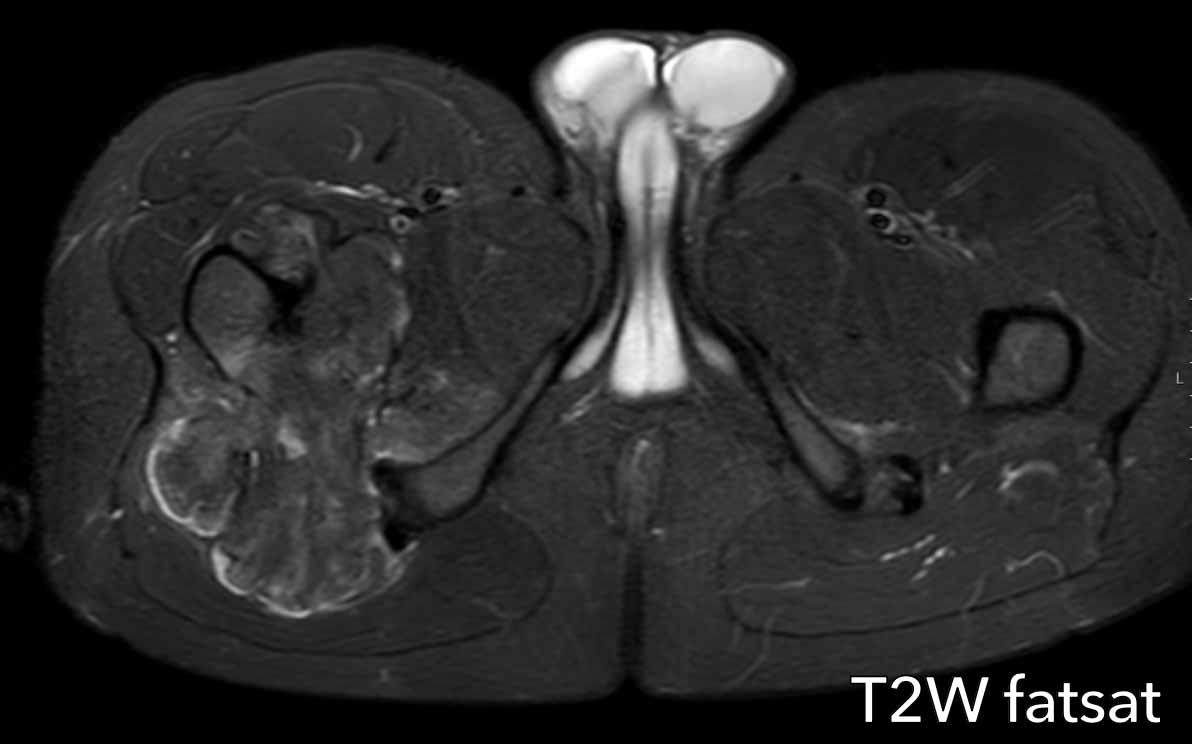

Hình ảnh

Có một tổn thương tiêu xương được xác định rõ >10 cm ở thân xương đùi đoạn gần với vôi hóa chất nền sụn dạng bỏng ngô.

Có sự giãn nở của xương, tuy nhiên không có dấu hiệu xói mòn vỏ xương rõ ràng hay phản ứng màng xương.

Kết luận

Dựa trên hình ảnh X-quang đơn thuần, khối u này có thể là một ACT hoặc sarcoma sụn độ cao hơn. Bước tiếp theo là thực hiện MRI để đánh giá đặc điểm chi tiết hơn.

MRI xác nhận bản chất sụn của khối u với các nốt sụn tăng tín hiệu trên T2 DIXON cho thấy ngấm thuốc kiểu vách-nốt sau tiêm thuốc tương phản.

Tuy nhiên, cũng có phù tủy xương đáng kể ở phía gần (mũi tên đen) và phản ứng màng xương kèm ngấm thuốc (mũi tên trắng).

Các đặc điểm này rất đáng ngờ cho chẩn đoán u sụn ác tính độ cao.

Hình ảnh T1 axial xác nhận tình trạng lõm vỏ xương phía trước sâu chiếm khoảng 1/3 vỏ xương, tức là lõm vỏ xương mức độ rộng (> 10% chu vi khối u).

Cắt bỏ đầu trên xương đùi đã được thực hiện.

Chẩn đoán cuối cùng: sarcoma sụn độ II